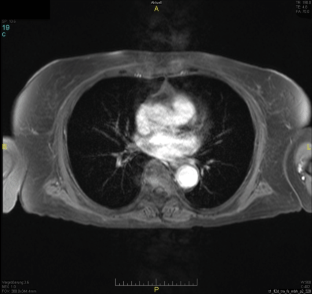

Abb. 1